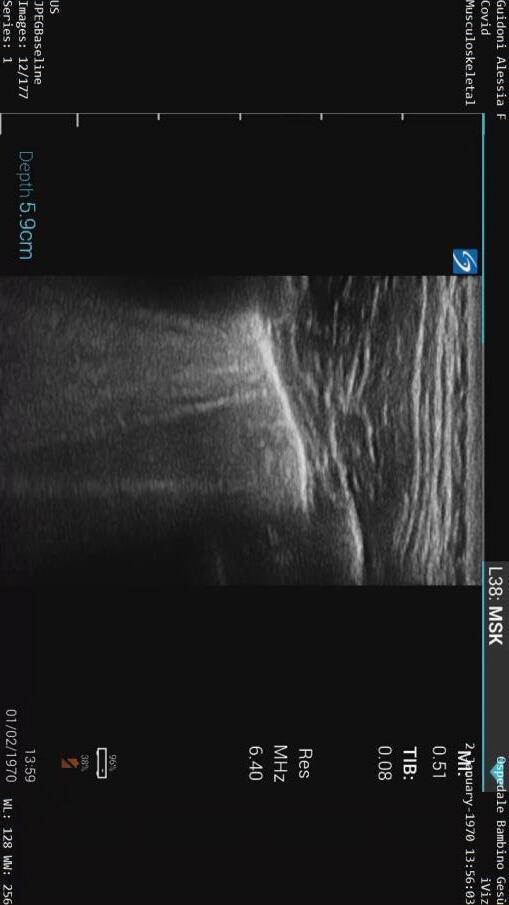

Intramural lymphocytic infiltrate

Chilblain-like lesions

19 cases

El Hachem JDV 2020

Perineural dermal inflammatory infiltrate

Thrombus